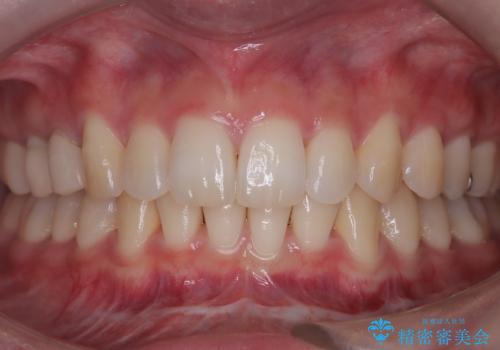

[ 矯正治療 ] 噛み合わせ前歯の見た目をきれいにしたい

![[ 矯正治療 ] 噛み合わせ前歯の見た目をきれいにしたいの症例 治療前](https://seimitsushinbi.jp/wp/wp-content/uploads/2025/08/IMG_7266-500x350.jpg?v=1754654745)

![[ 矯正治療 ] 噛み合わせ前歯の見た目をきれいにしたいの症例 治療後](https://seimitsushinbi.jp/wp/wp-content/uploads/2025/08/IMG_3482-500x350.jpg?v=1754654765)